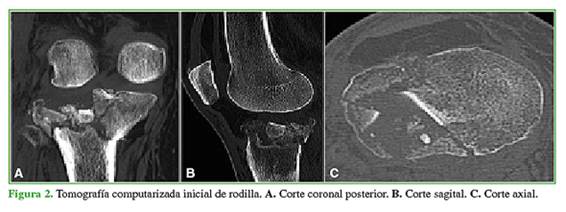

El par radiológico de rodilla y la tomografía computarizada revelan una fractura de platillo tibial clasificada como Schatzker VI (Figuras 1 y 2). Con la resonancia magnética de rodilla diferida, se diagnostica una lesión de tercer grado asociada del ligamento colateral medial.